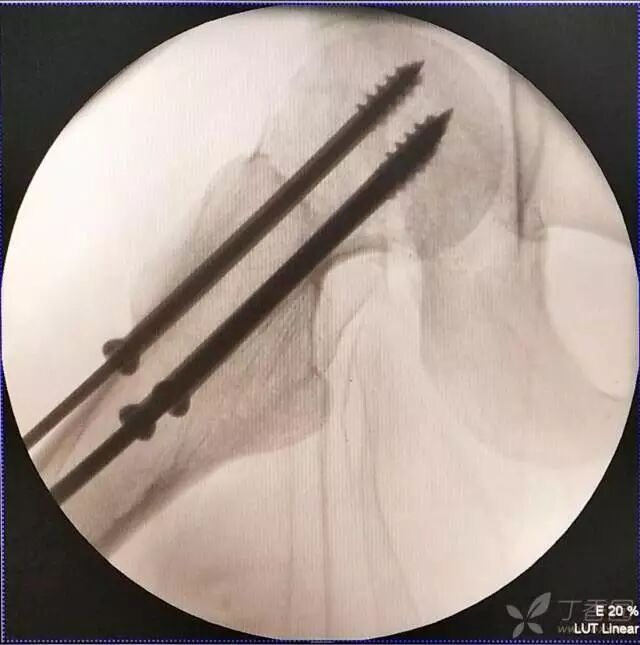

6. 然后依次打入倒品字上方的两枚导针

牵引床怎么用视频详解:如何不使用牵引床做好一台股骨颈骨折?_https://www.jmylbn.com_新闻资讯_第14张

8. 最后测深依次拧入合适长度的螺钉

牵引床怎么用视频详解:如何不使用牵引床做好一台股骨颈骨折?_https://www.jmylbn.com_新闻资讯_第17张